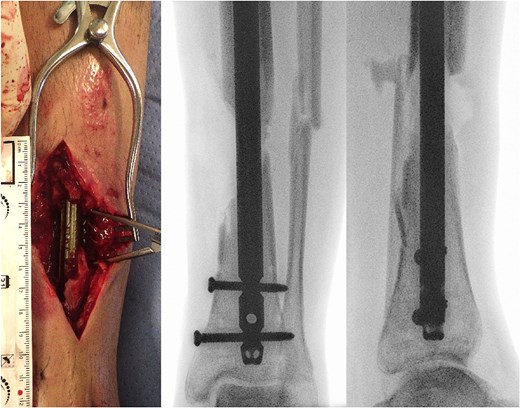

The patient then referred himself to our unit and we performed further extensive debridement of soft tissues and necrotic bone in repeated steps (Fig. 1). During the second revision, placement of gentamycin–polymethylmethacrylate antibiotic cement spacer was performed.

(a) Photography of intraoperative bone defect before graft cage implantation and (b) intraoperative X-rays of left lower extremity show segmental bone defect.

The workup showed an osseous defect of 4 cm laterally and 6 cm medially. The soft tissues required treatment as a 9 x 3cm measuring defect zone appeared. As all three arterial vessels (peroneal and anterior and posterior tibial arteries) were intact, an anterolateral thigh flap (ALT-flap) was applied to cover the soft tissue defect. The patient was discharged to a rehabilitation unit.